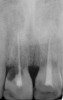

Figure 3  Periapical radiograph of implants in the Nos. 8 and 9 sites 3 years after placement. A bony peak was still present between the implants due to successful guided bone regeneration and favorable fixture spacing.

Figure 3

Figure 14  Initial periapical radiograph revealed internal root resorption of teeth Nos. 8 and 9 with almost complete horizontal severing of the crowns from the roots.

Figure 14